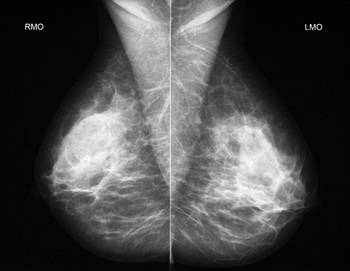

Mellkasi zárva keresztül több bár, kissé összenyomódik, majd, hogy egy sor felvett képek egy normál merevlemez vagy egyéb adathordozót.

Helyesen értelmezi a kép csak egy orvos és egy keskeny szakember. Mammolog csak lehet igaz jel a képeket a potenciálisan veszélyes területek, és pontos leírást. Az eredmény lehet:

A mammográfia érzékeli csak a jelenléte bizonyos struktúrák és azok helyét, és egyértelmű klinikai kép lehet beszerezni csak az Egyesült Államok után, további vizsgálatokat laboratóriumi vagy akár egy biopszia.